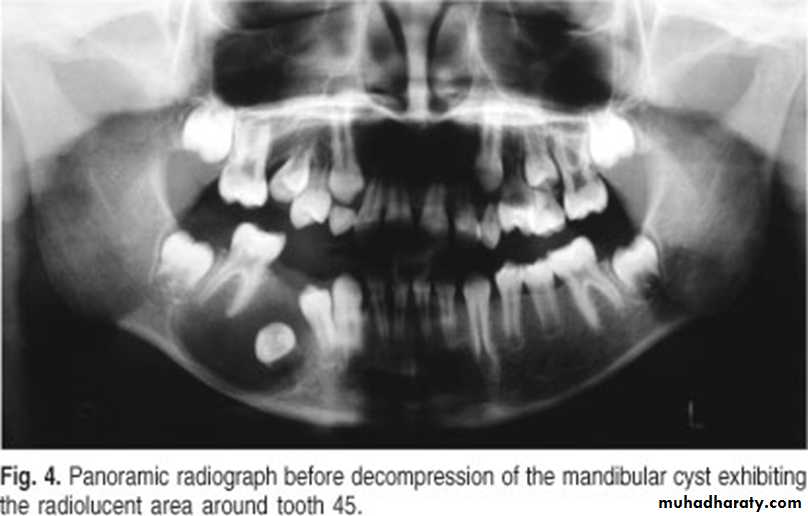

A 11-year-old female with swelling on the right side.

impacted canine